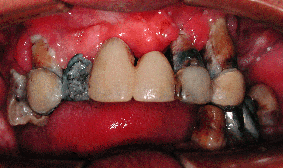

3.歯周病 歯周組織への影響 ・歯やその周囲に汚れがたまりやすくなる たばこの煙の中のタールは、俗に言うヤニとして歯の表面にこびりつきます。この部分には歯垢(プラーク)も沈着しやすくなり歯周病の発症や進行を助けます。 ・細菌に対する組織の抵抗力をが低下する ニコチンが歯肉や口腔粘膜からも吸収され、その付近の白血球などの免疫担当細胞の働きを鈍らせるため、細菌が体内に簡単に侵入して毒素などによる周りの組織の破壊を始めます.。そのため歯周病が発症したり、悪化し易くなります。 ・傷や治療を受けたところの治癒が悪くなる ニコチンにより、傷口をふさぐ細胞の動きが鈍くなりせっかく歯の治療を受けても良い結果が得られません。 | |

| たばこで歯が悪くなり、虫歯や入れ歯が多くなる | |

| 写真2 60代男性 喫煙歴40年 | 写真3 60代男性 喫煙歴30年 |